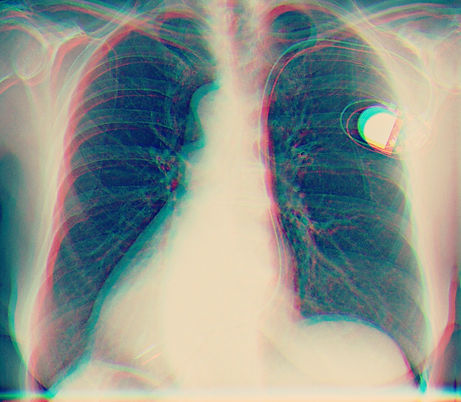

Im Gegensatz zu René und zu uns ist Fosca unsterblich. 1279 in Norditalien geboren, verleiht ihm ein Elixier ewiges Leben. Egal ob bei der Entdeckung Amerikas, als Berater von Kaisern, bei wissenschaftlichen Entdeckungen oder verstrickt in revolutionären Aktionen, er durchlebt immer wieder das menschliche Entstehen und Vergehen. Doch was bedeutet das menschliche Leben, wenn es nicht vergehen kann? Herzschrittmacher, Verjüngungskuren, künstliche Hüften und Schmerztherapien, wodurch und wie lange können wir uns vor unserer eigenen Sterblichkeit verstecken? Und wenn wir schon unser Leben verlängern wollen - koste es was es wolle - wofür lohnt sich ein unendliches Leben?